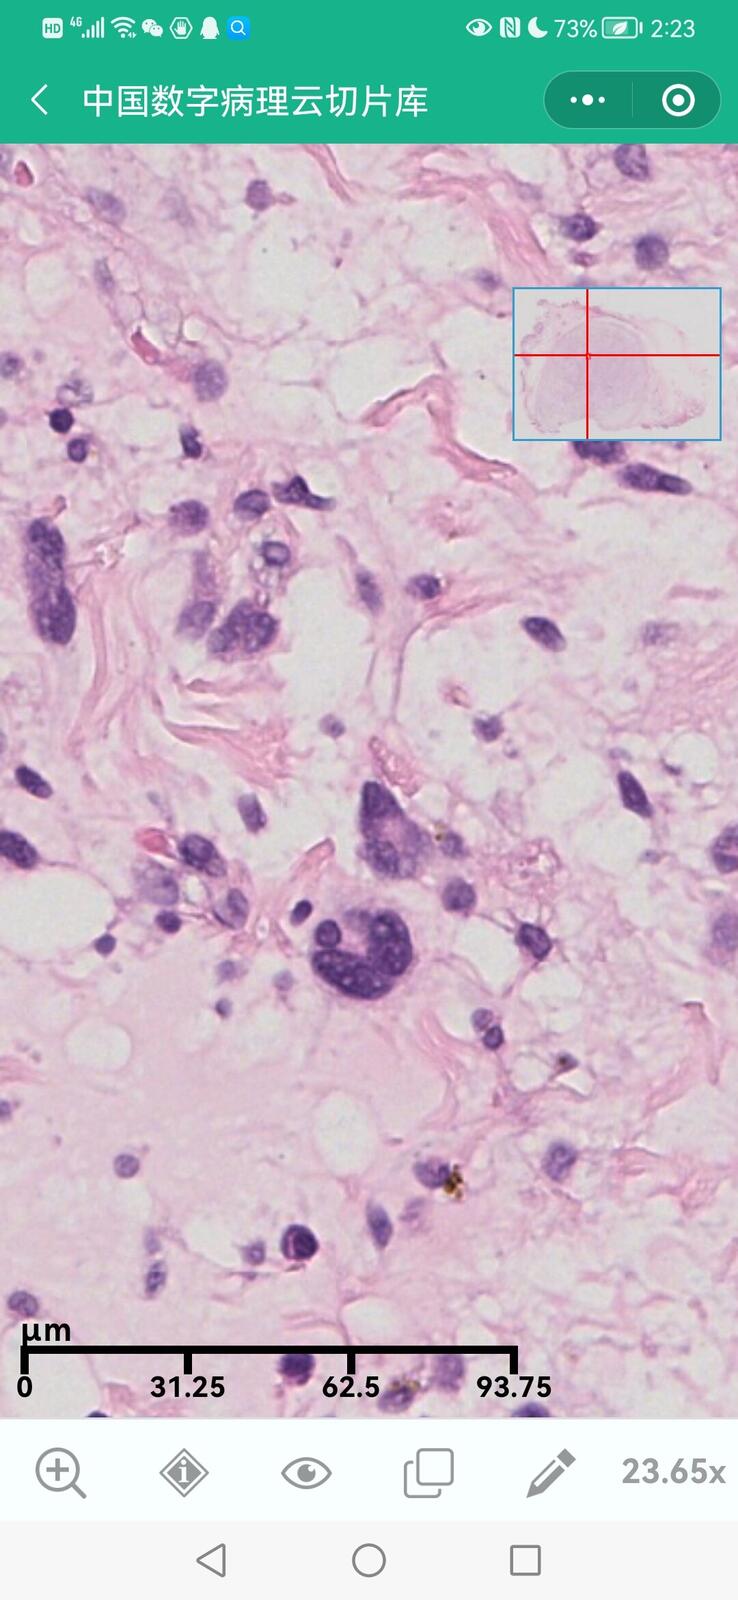

乳腺黏液性囊腺瘤伴导管内癌

乳腺多形性脂肪肉瘤

乳腺叶状囊肉瘤

乳腺分泌性癌(29岁)